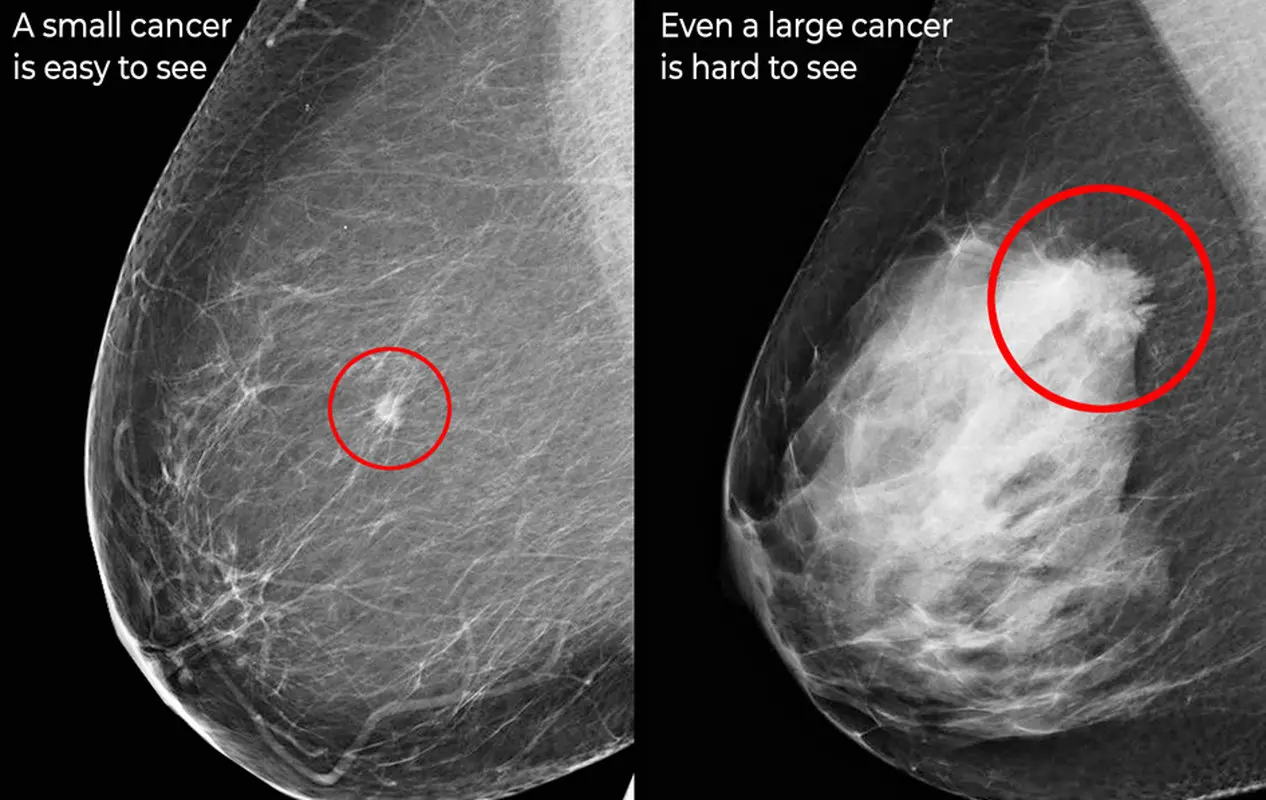

به تراکم بافت فیبر و غدد در پستان فیبروگلندولار می‌گویند. در واقع میزان تراکم فیبروگلندولار نشان دهنده تراکم بافت پستان است که در ماموگرافی نشان داده می‌شود. یکی از چالش‌های تراکم فیبروگلندولار آن است که رنگ فیبروگلندولار سفید بوده و بافت‌های مشکوک به سرطان نیز سفید رنگ هستند، بنابراین تشخیص توده‌های کوچک سرطانی می‌تواند سخت شود. یکی دیگر از چالش‌هایی که تراکم فیبروگلندولار ایجاد می‌کند آن است که چنانچه این تراکم بالا باشد، یعنی بافت سینه فرد متراکم‌تر باشد، احتمال بروز سرطان بالاتر می‌رود و این به معنای آن است که انجام معاینات دوره‌ای باید جدی‌تر گرفته شود. همچنین در افرادی که دارای تراکم فیبروگلندولار بیشتر هستند انجام ماموگرافی سه بعدی پیشنهاد بهتری است.

در تفسیر جواب ماموگرافی من نوشته شده که سینه‌ها "به صورت ناهمگونی متراکم هستند و شاید توده‌های کوچک را مبهم سازند". معنی این جمله عبارت است از اینکه بافت‌های شما نسبتاً متراکم هستند. این یک پدیده عادی است و جای نگرانی نیست. گاهی اوقات بافت‌های متراکم تفسیر صحیح جواب ماموگرافی را دشوار می‌سازند. در صورت لزوم، پزشک گزینه‌های عکس برداری مختلف را با شما مرور خواهد کرد.